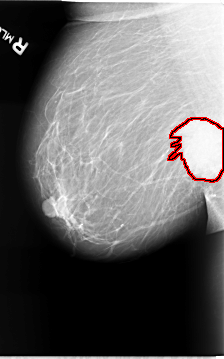

ics_version 1.0 filename B-3065-1 DATE_OF_STUDY 14 3 1994 PATIENT_AGE 69 FILM FILM_TYPE REGULAR DENSITY 2 DATE_DIGITIZED 15 9 1997 DIGITIZER LUMISYS LASER SEQUENCE LEFT_CC LINES 5880 PIXELS_PER_LINE 3664 BITS_PER_PIXEL 12 RESOLUTION 50 NON_OVERLAY LEFT_MLO LINES 5856 PIXELS_PER_LINE 3864 BITS_PER_PIXEL 12 RESOLUTION 50 NON_OVERLAY RIGHT_CC LINES 5704 PIXELS_PER_LINE 3504 BITS_PER_PIXEL 12 RESOLUTION 50 OVERLAY RIGHT_MLO LINES 5736 PIXELS_PER_LINE 3576 BITS_PER_PIXEL 12 RESOLUTION 50 OVERLAY |

FILE: B_3065_1.RIGHT_MLO.OVERLAY TOTAL_ABNORMALITIES 1 ABNORMALITY 1 LESION_TYPE CALCIFICATION TYPE PLEOMORPHIC DISTRIBUTION CLUSTERED LESION_TYPE MASS SHAPE IRREGULAR MARGINS SPICULATED ASSESSMENT 5 SUBTLETY 5 PATHOLOGY MALIGNANT TOTAL_OUTLINES 1 BOUNDARY |